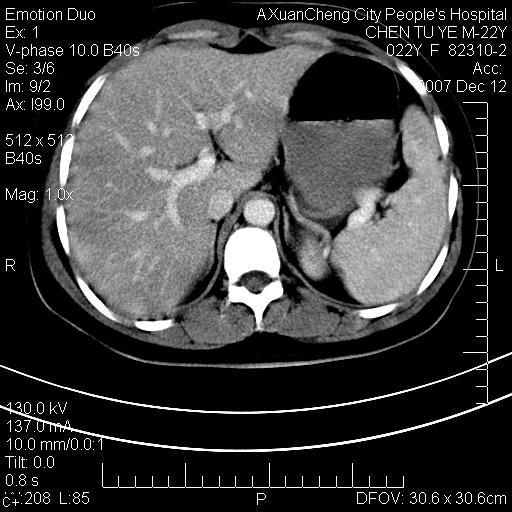

超声提示肝右前叶占位,约2.5cm.

各位战友看看病灶在什么地方,可是右前叶进肝裂部低密度影,平扫ct值约10以下,增强后增高明显

1 脾大,慢性肝损伤. 2 肝脏脂肪侵润.  3 你所指的部位疑点,我没看出有问题.

脂肪肝.楼主所指部位不考虑异常,为肝圆韧带影.

1 脾大,慢性肝损伤. 2 肝脏脂肪侵润.

脂肪肝,脾大

平扫与增强ct值差>10hu的话,应该列为高度疑似病例,我们的职责就是不能放过这样小的病灶.再次b超对比

确定是否同一病灶!运到伪影我坚决反对!

不均匀脂肪浸润,版主所说的病灶为肝园韧带服着点。

考虑肝圆韧带。